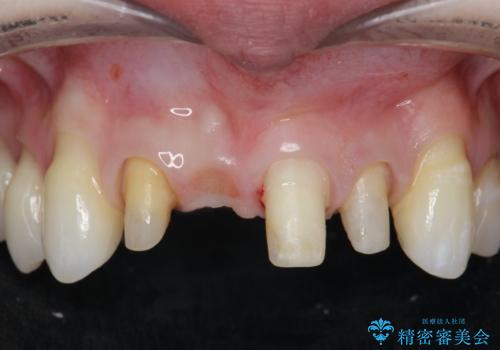

吸収し喪失した前歯、ブリッジによる審美性の回復

- 前医に前歯の吸収による抜歯の必要性を伝えられ、前歯の審美的な改善・治療を求めて来院されました。

CT撮影を行った結果、右上前歯は吸収が進み抜歯が必要な状態です、

抜歯をせず放置すると、より吸収が進み臨在する歯にも悪影響を及ぼしてしまう可能性が考えられます。

上顎4前歯は、根管治療の既往があり、虫歯も見られたことからブリッジによる治療で審美性の回復を行うとともに臨在歯の虫歯もセラミック治療を行っていきます。